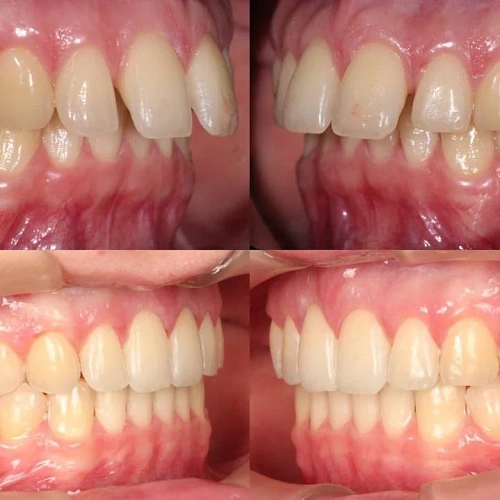

Нарушение соотношения челюстей и неправильное положение зубов — зубные ряды смыкались некорректно, зубы стояли со смещением.

Зубы выровнены, смыкание нормализовано. Установлены несъёмные ретейнеры на обе челюсти, сняты сканы для ретенционных кап. Консультация ортопеда запланирована на более поздний срок.

Проблема: Пациентку беспокоило неправильное смыкание зубов и их положение — ряды не сходились как нужно, зубы стояли со смещением. Это влияло и на внешний вид, и на то, как распределялась нагрузка при жевании.

Решение: Поставили прозрачные элайнеры 3D Smile на обе челюсти. Начали с набора из 34 кап, но в процессе стало понятно, что для полной коррекции нужна доработка — заказали дополнительный набор из 28 кап. Это нормальная ситуация: организм реагирует на перемещение зубов индивидуально, и заранее предсказать точное количество кап до последней штуки невозможно. В итоге 62 капы за 32 месяца — зубы встали на место, смыкание пришло в норму. Параллельно следили за гигиеной, чтобы дёсны оставались здоровыми на протяжении всего лечения.

Основной набор из 34 кап выполнил бо́льшую часть работы, но для финальной коррекции смыкания понадобился дополнительный комплект. Это не редкость — зубы двигаются с разной скоростью, и последние доли миллиметра часто требуют доработки. В итоге получили стабильный результат, который зафиксировали ретейнерами.